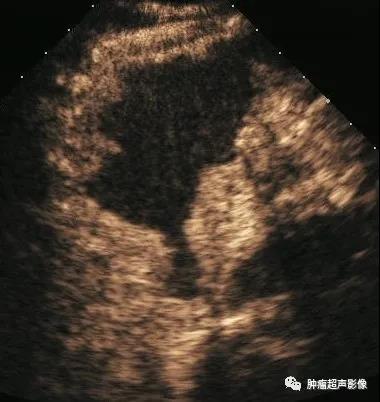

胃淋巴瘤:矛盾现象:肿块虽大,但是并未明显向外侵犯,增厚的胃壁厚薄相对均匀,黏膜及浆膜反射界面比较光整,胃外形规则(病例来自云南胃肠超声群会诊病例)